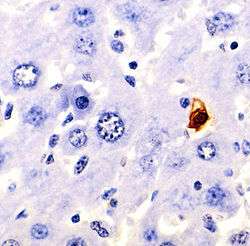

Methods for distinguishing apoptotic from necrotic (necroptotic) cells

In order to perform analysis of apoptotic versus necrotic (necroptotic) cells, one can do analysis of morphology by time-lapse microscopy, flow fluorocytometry, and transmission electron microscopy. There are also various biochemical techniques for analysis of cell surface markers (phosphatidylserine exposure versus cell permeability by flow fluorocytometry), cellular markers such as DNA fragmentation[53] (flow fluorocytometry), caspase activation, Bid cleavage, and cytochrome c release (Western blotting). It is important to know how primary and secondary necrotic cells can be distinguished by analysis of supernatant for caspases, HMGB1, and release of cytokeratin 18. However, no distinct surface or biochemical markers of necrotic cell death have been identified yet, and only negative markers are available. These include absence of apoptotic markers (caspase activation, cytochrome c release, and oligonucleosomal DNA fragmentation) and differential kinetics of cell death markers (phosphatidylserine exposure and cell membrane permeabilization). A selection of techniques that can be used to distinguish apoptosis from necroptotic cells could be found in these references.[54][55][56]